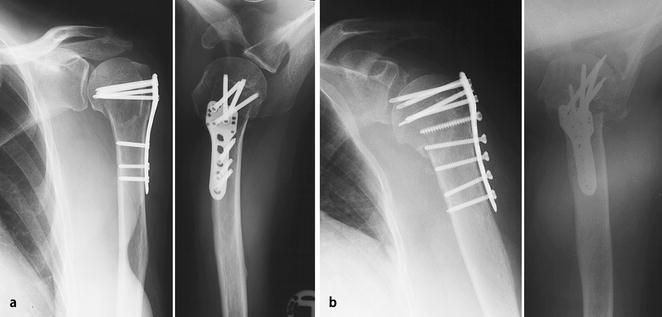

Therapie der proximalen Humerusfraktur mit winkelstabiler Plattenosteosynthese